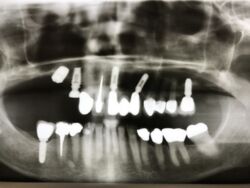

Kieler Patientin zur Versorgung einer Implantatbrückenrekonstruktion

Nach erfolgreicher Osseointegration erfolgt heute die Versorgung der beiden Implantate mit einer Brückenkonstruktion.

Auch in diesem Fall müssen verschiedene Entwicklungsstufen eines Implantatsystems miteinander kombiniert werden.